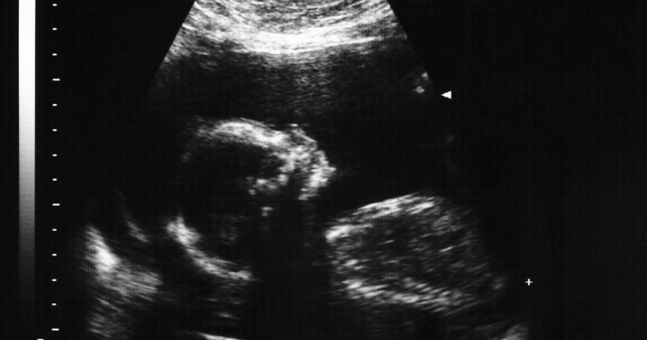

The Health Service Executive is to publish a full nationwide review of maternity services complaints.

According to RTÉ Investigates, the document, which will take in complaints made at every maternity hospital in the country, will be published and distributed to every family affected on Tuesday, May 23 at noon.

The Maternity Clinical Complaints Review was commissioned by the HSE Acute Hospitals Division three years ago in the aftermath of the RTÉ Investigates programme, Fatal Failures, broadcast in January 2014.

The television programme uncovered a series of baby deaths at the Midlands Regional Hospital Portlaoise, sparking a radical overhaul of maternity care in Ireland.